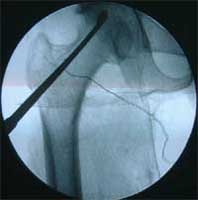

股骨头缺血性坏死MRI显示坏死区                  微创手术方法,采用隧道减压刮除死

BMP植入,异体骨支撑,恢复形态       手术后24个月X线片,关节塌陷未加重,关节功能良好,无疼痛